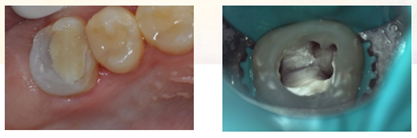

复诊,无不适,去除冠部暂封,试主牙胶尖,拍摄X-ray。

iROOT SP糊剂单尖法根充四根管,SDR树脂髓腔充填,拍摄X-ray,显示根管充填完好。

牙体预备制取26高嵌体工作模型

复诊,无不适,上橡皮障,粘接树脂高嵌体